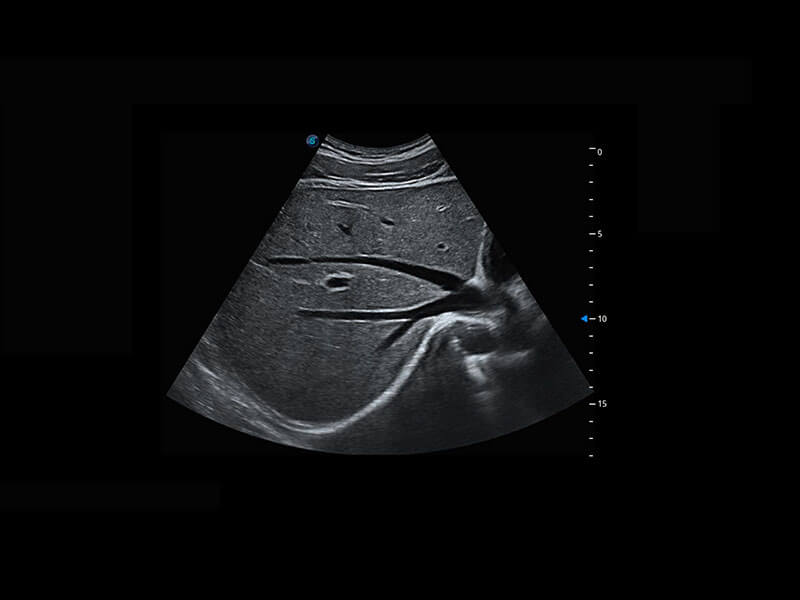

腔内三维-宫内节育器

腔内三维-光影成像